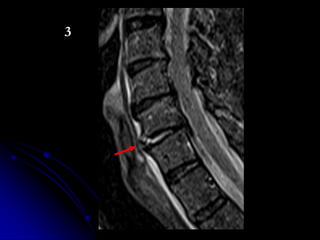

C-SPINE IMAGING

ALGORITHM

• CT

• MRI (depending upon Hx, PE, CT

findings)

• FLEX/EXT imaging (x-ray or CT

depending on CT/MRI findings and clinical

presentation)

1 2 3 4

WHICH PATIENT HAS ACUTE FX WITH SUBSEQUENT FUSION?

3

T6 T6

L2